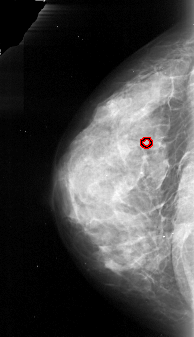

A_1092_1.RIGHT_CC

RIGHT_CC LINES 4111 PIXELS_PER_LINE 2206 BITS_PER_PIXEL 16 RESOLUTION 42 NON_OVERLAY

FILE: A_1092_1.LEFT_CC.OVERLAY

TOTAL_ABNORMALITIES 1

ABNORMALITY 1

LESION_TYPE CALCIFICATION TYPE PUNCTATE DISTRIBUTION CLUSTERED

ASSESSMENT 4

SUBTLETY 1

PATHOLOGY MALIGNANT

TOTAL_OUTLINES 1

BOUNDARY